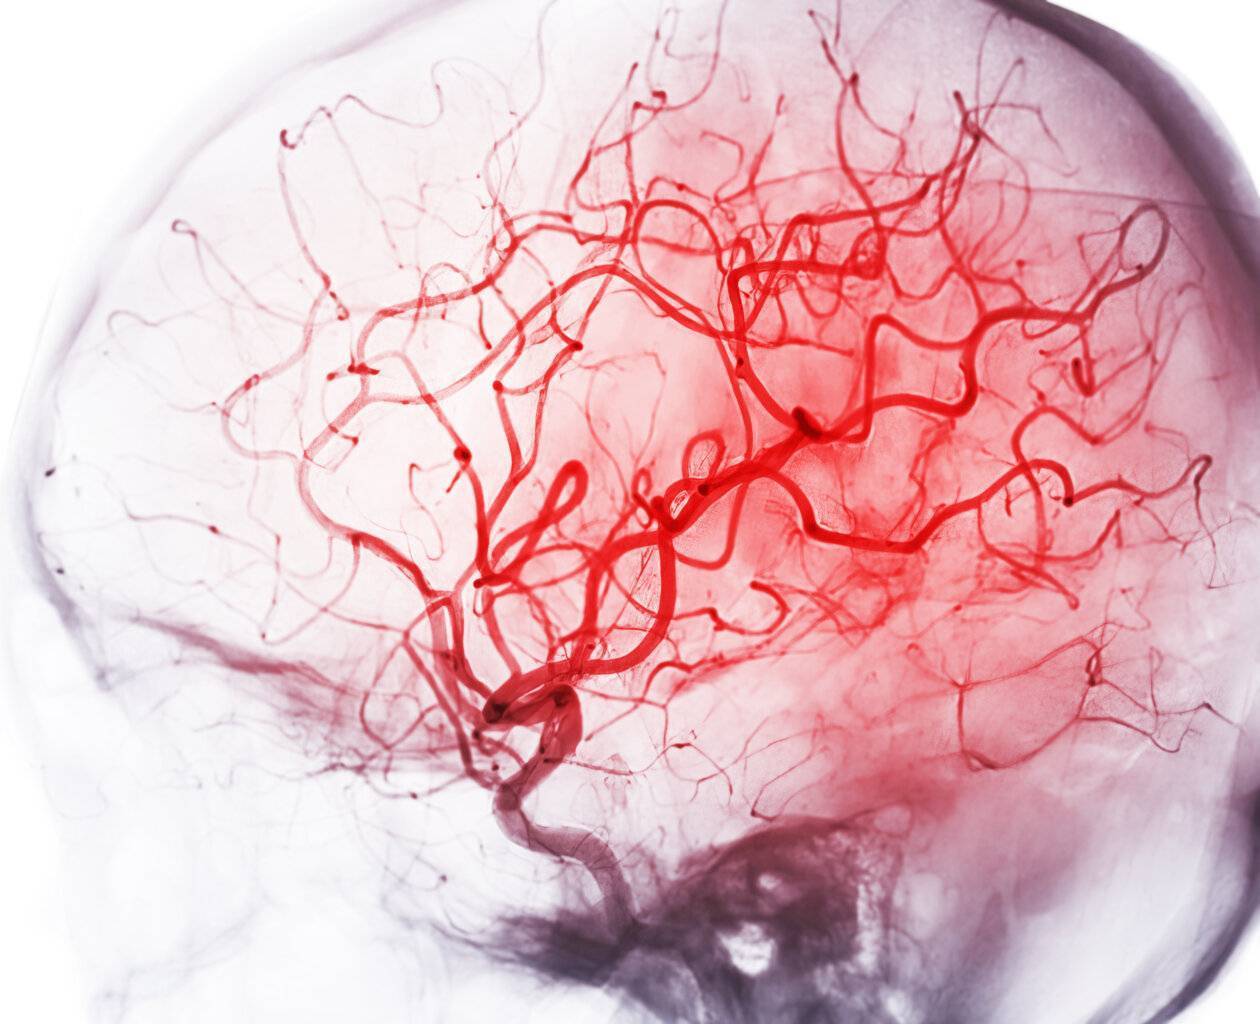

Die Computertomografie kombiniert Röntgentechnologie mit computerunterstützter Bildverarbeitung, um Querschnittsbilder des Körpers zu erstellen. Patienten werden in einer Röhre gescannt, in der Röntgenstrahlen aus verschiedenen Winkeln abgegeben werden. Der Computer setzt diese einzelnen Schichtbilder zu einem dreidimensionalen Bild zusammen. CT-Scans bieten eine detaillierte Darstellung von Knochen, Organen, Blutgefäßen und Weichteilen und sind besonders nützlich bei der Diagnose von Verletzungen, Tumoren, Blutungen oder Gefäßerkrankungen. Sie kommen auch bei der Krebserkennung und -überwachung sowie in der Notfalldiagnostik zum Einsatz.

Diese Methode kombiniert bildgebende Verfahren mit invasiven Eingriffen. Interventionelle Radiologen verwenden Röntgen, CT oder Ultraschall, um Eingriffe durchzuführen, die früher nur durch offene Chirurgie möglich waren. Typische Verfahren sind das Setzen von Kathetern, das Aufweiten von verengten Blutgefäßen (Ballondilatation), das Einsetzen von Stents oder das gezielte Einbringen von Medikamenten in Tumore. Auch Gewebeproben (Biopsien) können unter bildgebender Kontrolle entnommen werden.

- Kardiologische Diagnostik: Verfahren wie CT-Koronarangiographie ermöglichen die Früherkennung von Herzkrankheiten.